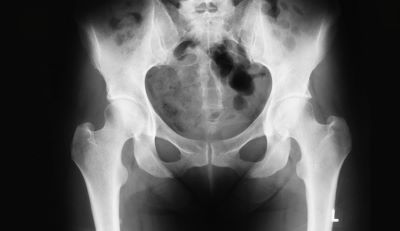

来院された患者様の中には、手術までしたのに来院する今日まで、一向に症状が改善されなかった辛さを私に説明するために、ボルトで固定された背骨のレントゲン写真を持参される方がいらっしゃいます。

「イメージ画像」

この患者様を担当した病院はこんな安易に手術をしてしまうという判断を自分の両親、家族にも自信をもって本当にするんでしょうか?その時、私は何とも言えない強い憤りを感じます。『なぜ、もっと早くこの人に出会えなかったのだろうか?』と。